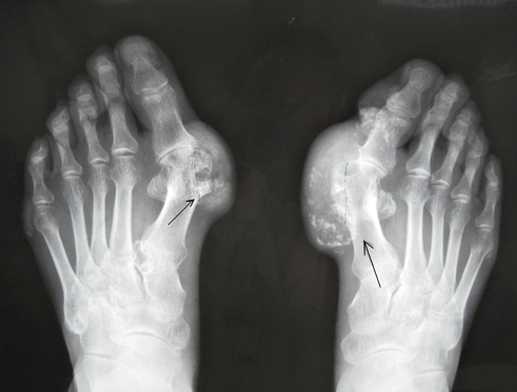

痛风是一种由于嘌呤生物合成代谢增加,尿酸产生过多或因尿酸排泄不良而致血中尿酸升高,尿酸盐结晶沉积在关节滑膜、滑囊、软骨及其他组织中引起的反复发作性炎性疾病。它是由于单钠尿酸盐结晶或尿酸在细胞外液形成超饱和状态,使其晶体在组织中沉积而造成的一组异源性疾病。

本病以关节液和痛风石中可找到有双折光性的单水尿酸钠结晶为其特点。其临床特征为:高尿酸血症及尿酸盐结晶、沉积所致的特征性急性关节炎、痛风石、间质性肾炎,严重者见关节畸形及功能障碍,常伴尿酸性尿路结石。